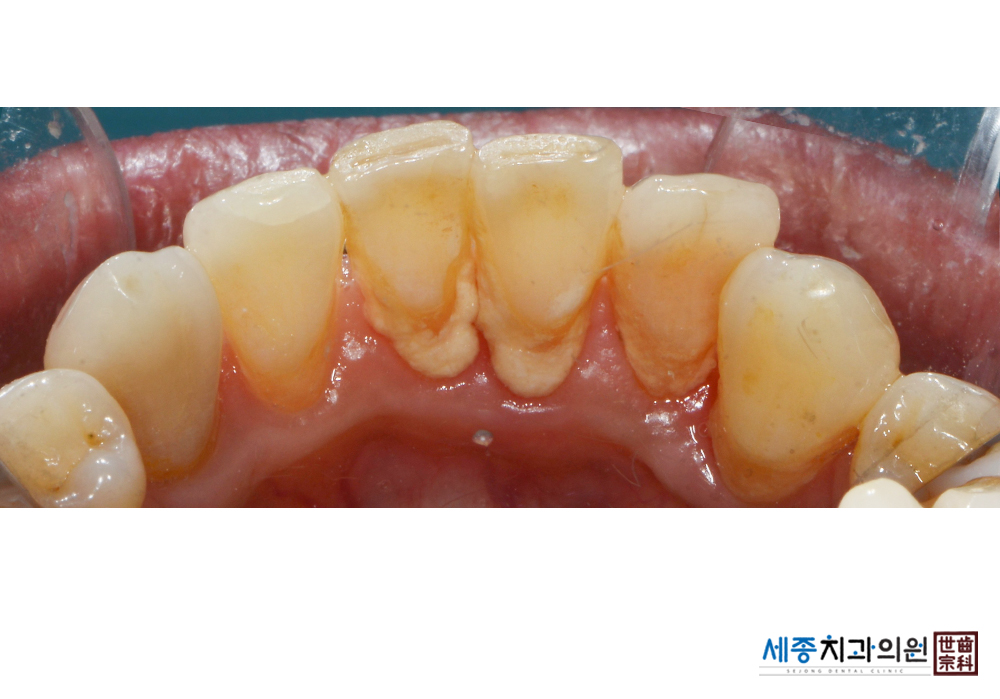

[스케일링] 치주질환 예방 스케일링

치료전 : 2020-01-17

가글마취&저주파 스켈러를 사용한 스케일링